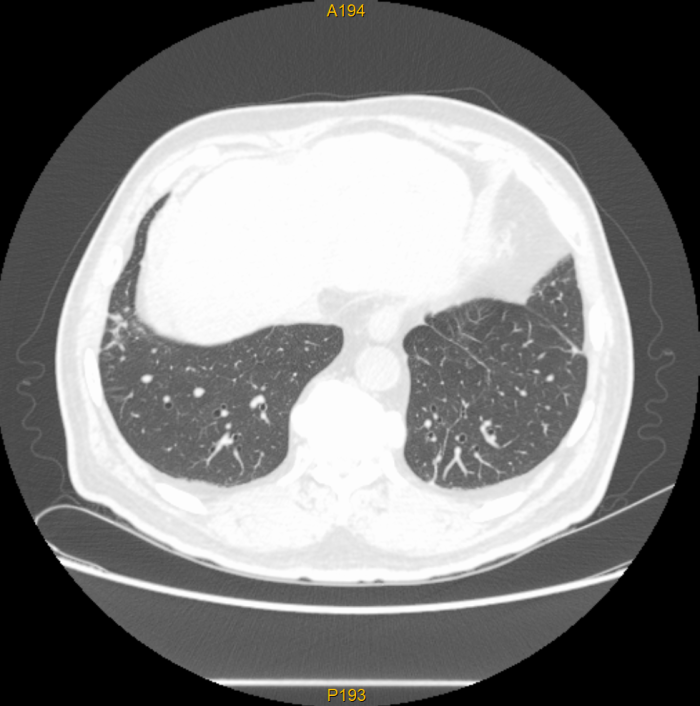

近日,我院肿瘤放射治疗科应用体部立体定向放疗(SBRT)技术,为一名胆管癌肺转移患者实施了精准放射治疗。通过制定规范的放射治疗计划,肺部两个转移病灶在接受SBRT治疗后基本消失,复查影像显示肿瘤已得到良好控制,彰显了精准放疗技术在肿瘤治疗中的独特优势。

该患者为胆管癌术后出现肺转移,两个转移病灶分别位于右肺上叶后段(大小26*25mm)及右肺下叶前基底段(大小28*30mm)。此前,患者已接受肝动脉化疗灌注(HACI)及多疗程全身化疗,但肺部病灶仍有增大趋势,治疗一度陷入困境。

治疗过程非常顺利,患者无明显不适。治疗结束后复查,两个肺部转移病灶已基本消失,显示出SBRT在局部肿瘤控制方面的绝对优势。这一结果不仅为患者带来了新的希望,也再次印证了精准放疗在肿瘤综合治疗中的重要地位。